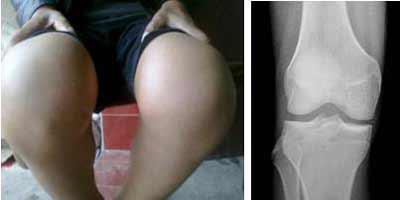

(图:患者治疗后膝关节红肿消失,屈伸自如)

治疗四十分钟后,赵先生就感觉四肢关节疼痛减轻了不少。两个疗程的治疗后,赵先生膝关节肿胀消除,关节处未见皮肤发红,关节晨僵现象消失,四肢关节活动自如,膝关节能够自由屈伸。

主治医生采用华中地区全力引进的HD-热层析检测系统,检测患者关节炎性介质消失,四肢关节无疼痛现象。